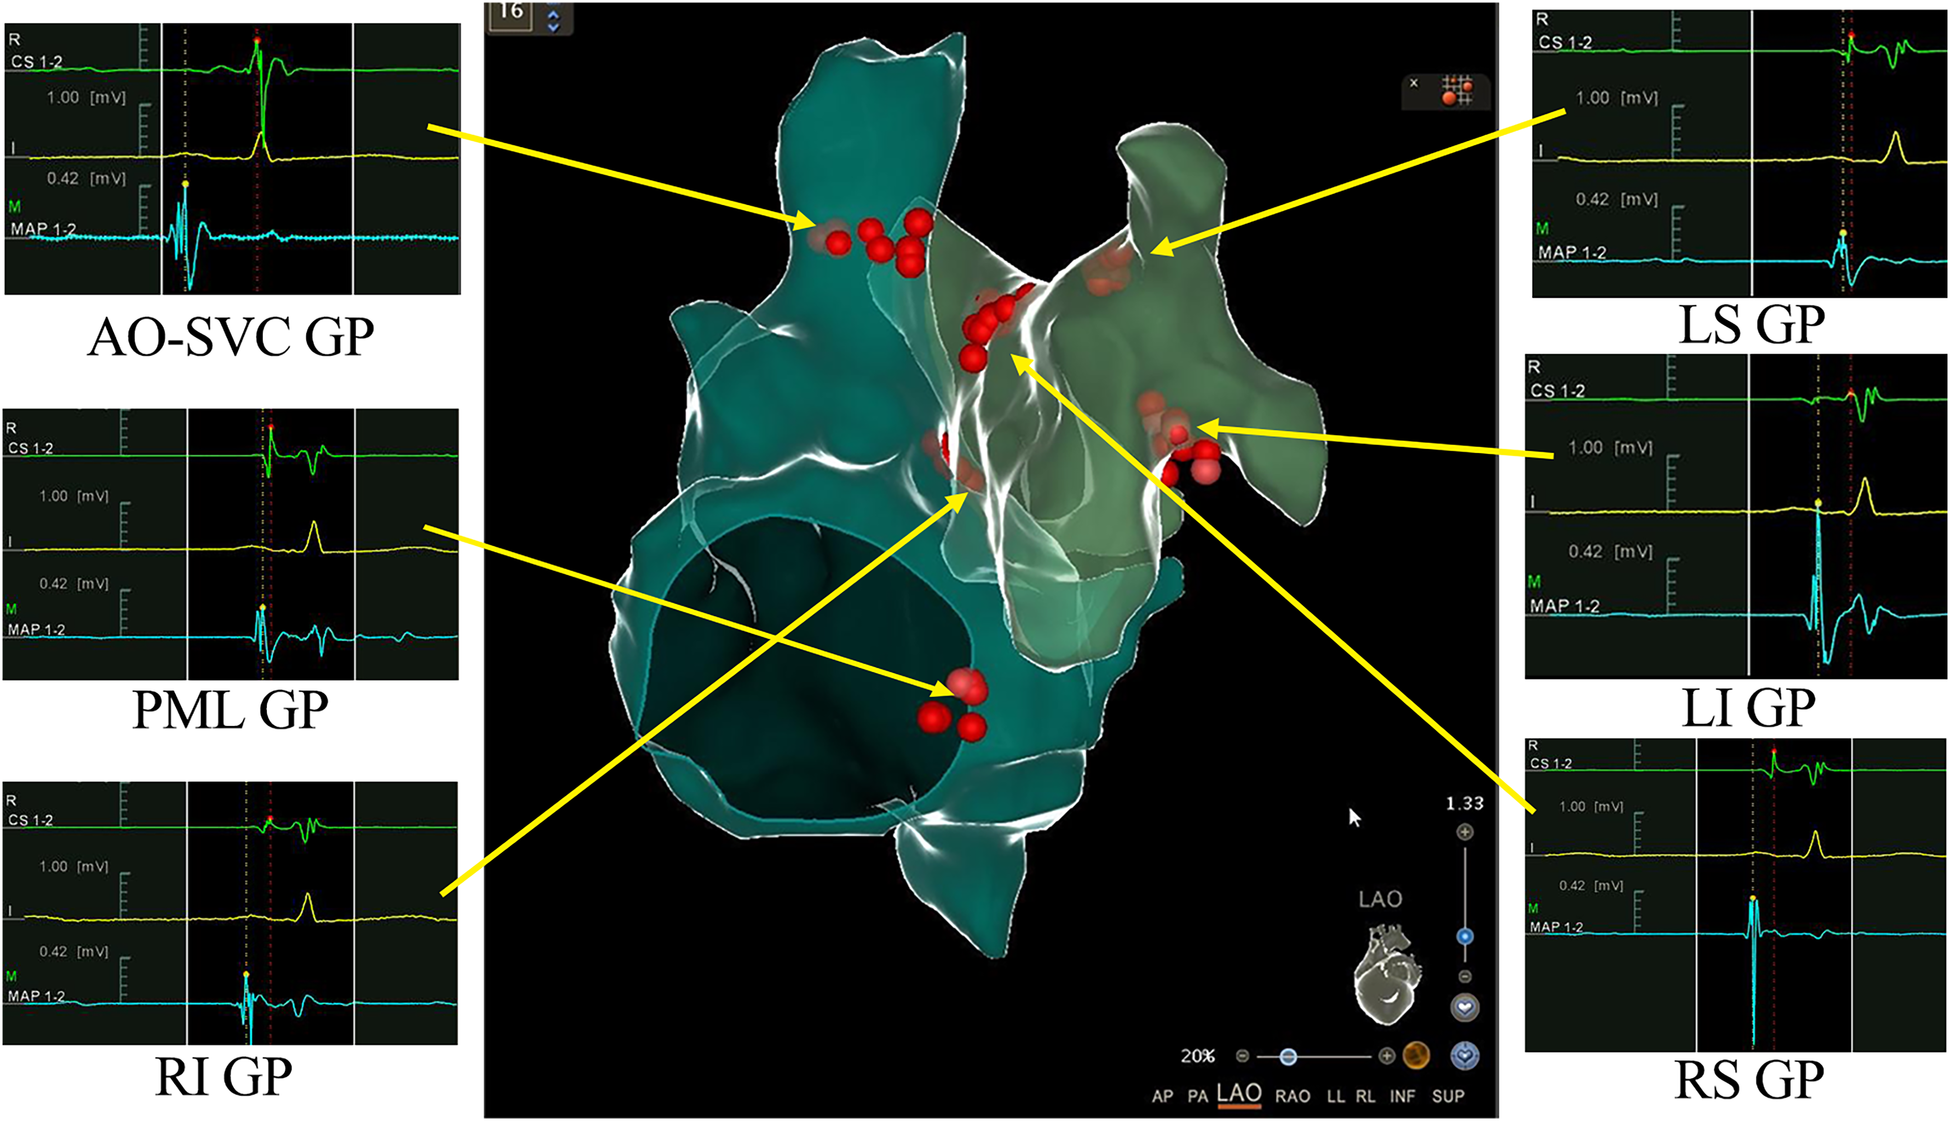

Figure 2

3D view of ganglionated plexus (GPs) groups distribution and ablation in the right and left atrium. Combined 3-dimensional electroanatomic mapping and radiofrequency (RF) ablation based on presence of fragmented/fractionated potentials in sinus rhythm. Red dots indicate RF application on the GPs sites. AO-SVC GP, aorto-superior vena cava GP; PML GP, posteromedial left GP; LS GP, left superior GP; LI GP, left inferior GP; RS GP, right superior GP; RI GP, right inferior GP.

The patient was consulted by the neurology department at the very beginning and NMOSD was suspected. But considering that her symptoms and signs were not typical, we finally decided not to use methylprednisolone before her head MRI test done. However, head and neck MRI could not be performed because implanted temporary pacemaker and the lead were non-MR-conditional. After detailed discussion and counseling, patient and family agreed to proceed with CNA. The procedure was performed under Moderate sedation and routine electrophysiological testing was completed. The ganglionated plexus groups were mapped and ablated using a 3D electroanatomic mapping system, guided by anatomy and fragmented potentials. (CARTO3 Version 6; Biosense Webster, Diamond Bar, CA, USA) and a Thermocool® SmartTouch (Biosense Webster, Diamond Bar, CA, USA) irrigation catheter. The right atrium was initially reconstructed. Local fragmented intra-cardiac electrograms in the areas of aorto-superior vena cava GP and posteromedial left GP were eliminated (Figure 2). The left atrium was reconstructed and fragmented potentials were mapped. Ablation delivered at the targeted GPs (left superior GP, left inferior GP, right superior GP, and right inferior GP) (Figure 2). After ablation, the resting sinus rate increased from 54 bpm to 68 bpm, the long R-R interval > 2.0 s following hiccups was no longer present and temporary pacemaker was removed. There was no major complication related to the procedure. Two days after CNA procedure, persistent hiccup, vomit, and anorexia were still present and refractory to conventional medical therapy, but the episodes of dizziness and syncope had completely resolved. A 48-h Holter monitoring confirmed no R-R interval >2.0 s. MRI of the skull and spinal cord revealed a lesion at dorsal medulla oblongata (Figure 3). As the cerebrospinal fluid was tested positive for anti-AQP4 antibody, she was diagnosed as NMOSD. Considering the patient's low BMI (19.3) and the need for anti-coagulation therapy after CNA, methylprednisolone pulse therapy (800 mg per day instead of 1,000 mg) was given for five days and then changed to oral prednisolone with simultaneously ofatumumab for sequential immunosuppressive therapy. Her symptoms resolved and was discharged five days later with prednisolone (45 mg per day for the first 2 weeks, then gradually reducing dosage under the supervision of a physician), levothyroxine sodium 50 Ug per day and Edoxaban 30 mg per day for 2 months.